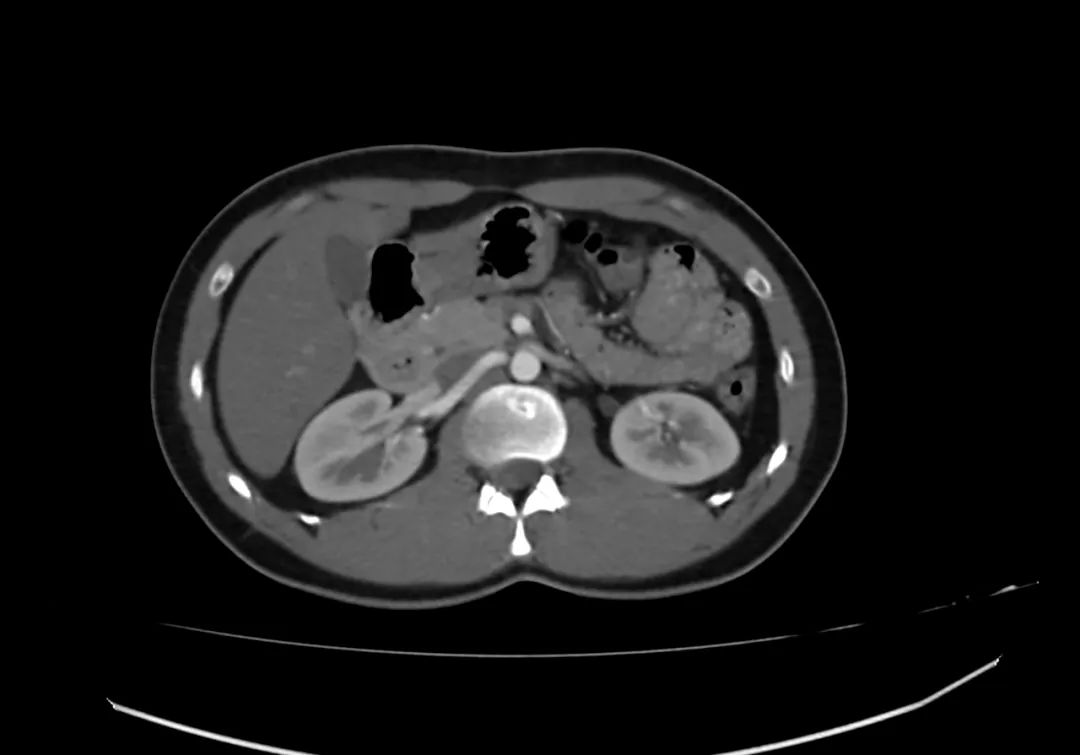

动脉期上腹部轴向增强图像显示胰腺完全包围十二指肠第二部,与完全性环状胰腺一致。